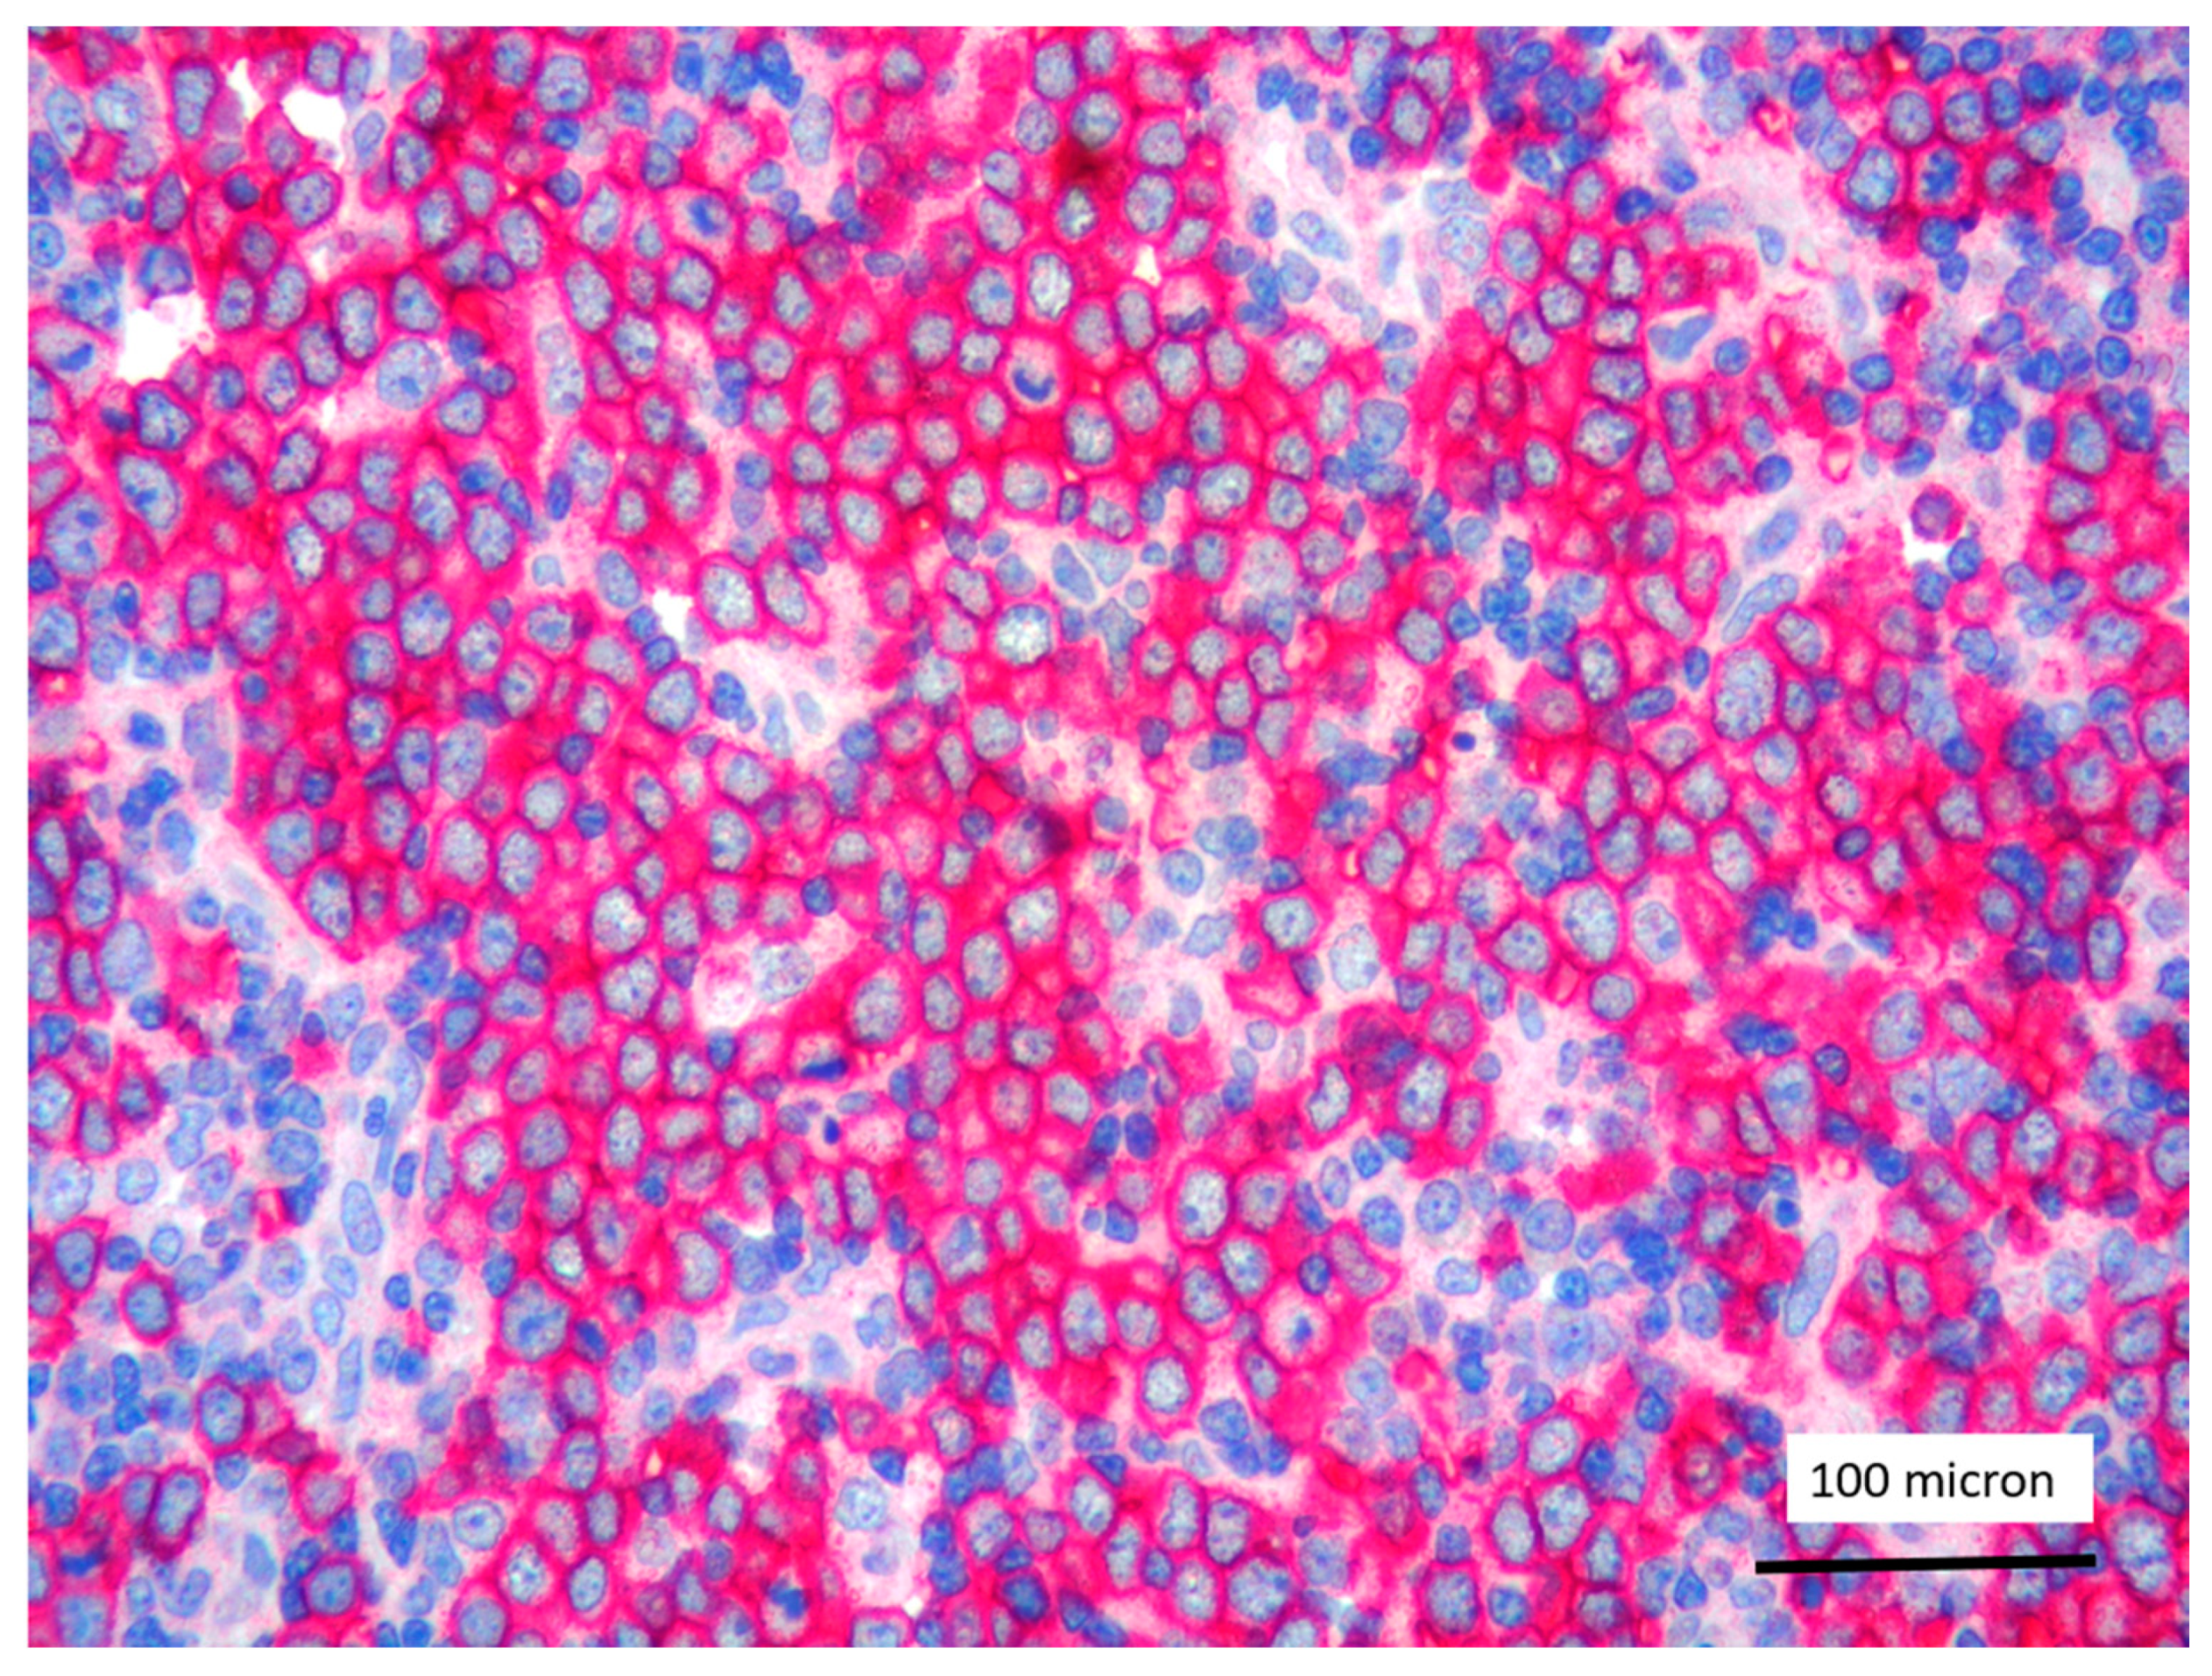

In all the cases, the lymph node histology and immunohistochemical profile were consistent with T-LBL diagnosis. The nodal architecture was effaced by a diffuse proliferation of medium-sized cells with dispersed chromatin and scarce cytoplasm (Figure 1) with high proliferative fraction and usually positive for TdT (Figure 2), CD1a and T-cell markers such as CD3 (Figure 3), CD2, CD8, CD5, CD7. B-cell markers (CD79α, CD20, PAX5 and CD22) were mostly negative; a weak CD79α co-expression was noted in 2/11 cases; myeloid (MPO, CD117, CD68KP1) and monocytic (CD68PGM1) markers were negative. In 5/11 cases, a minor component of immature myeloid cells was identified (Figure 4). Aggregates of mature eosinophils (Figure 5) admixed to the lymphoblastic proliferation were noted in 5/11 cases, whereas clusters of proerytroblasts (Figure 6 and Figure 7) were identified within T-LBL in 1/11 cases. Unexpectedly, LMO2 immunostaining was found to be negative in 9/11 T-LBLs (Figure 8); in the remaining 2 cases, LMO2 was partially expressed (less than 30% of cells) with either moderate or low degree of intensity, respectively (Figure 9).

T-LBL almost universally overexpress LMO2 [14,15]. Unexpectedly, in our series, the majority of T-LBL occurring in the context of M/LNs-Eo was LMO2 negative, with only 2 cases showing partial LMO2 expression with moderate and low degree of intensity, respectively. Jevremovic et al. reported that LMO2 represents a marker commonly expressed by T-LBL and absent in thymocytes of normal thymus and thymomas [15]. Since there is no specific immunophenotypic profile to distinguish thymocytes or thymic epithelial tumors from neoplastic T lymphoblasts, LMO2 is currently considered a useful marker in discriminating thymoma from T-LBL, being almost universally expressed in T-LBL [15]. Recently Brar et al. identified LMO2 as a sensitive and specific marker for differentiating T-LBL from iT-LBP, which were found to be LMO2-negative [16]. The absence of LMO2 expression in iT-LBP was considered by Brar et al. consistent with a thymic origin for iT-LBP as T-lymphoblasts in the thymus do not express LMO2 [16].

In our study, we would suggest that LMO2 immunostaining, as part of the diagnostic panel for T-LBL, may represent a potentially useful marker to identify T-LBL developing in the context of M/LNs-Eo. In this particular setting, T-LBL shows an immunohistochemical profile overlapping with cortical thymocytes and iT-LBP, possibly reflecting different molecular patterns involved in the pathogenesis of T-LBL arising in the setting of M/LNs-Eo.

Figure 8. LMO2 negativity of T-LBL; endothelial cells as positive LMO2 controls (case 1, immunostaining, magnification 400×).